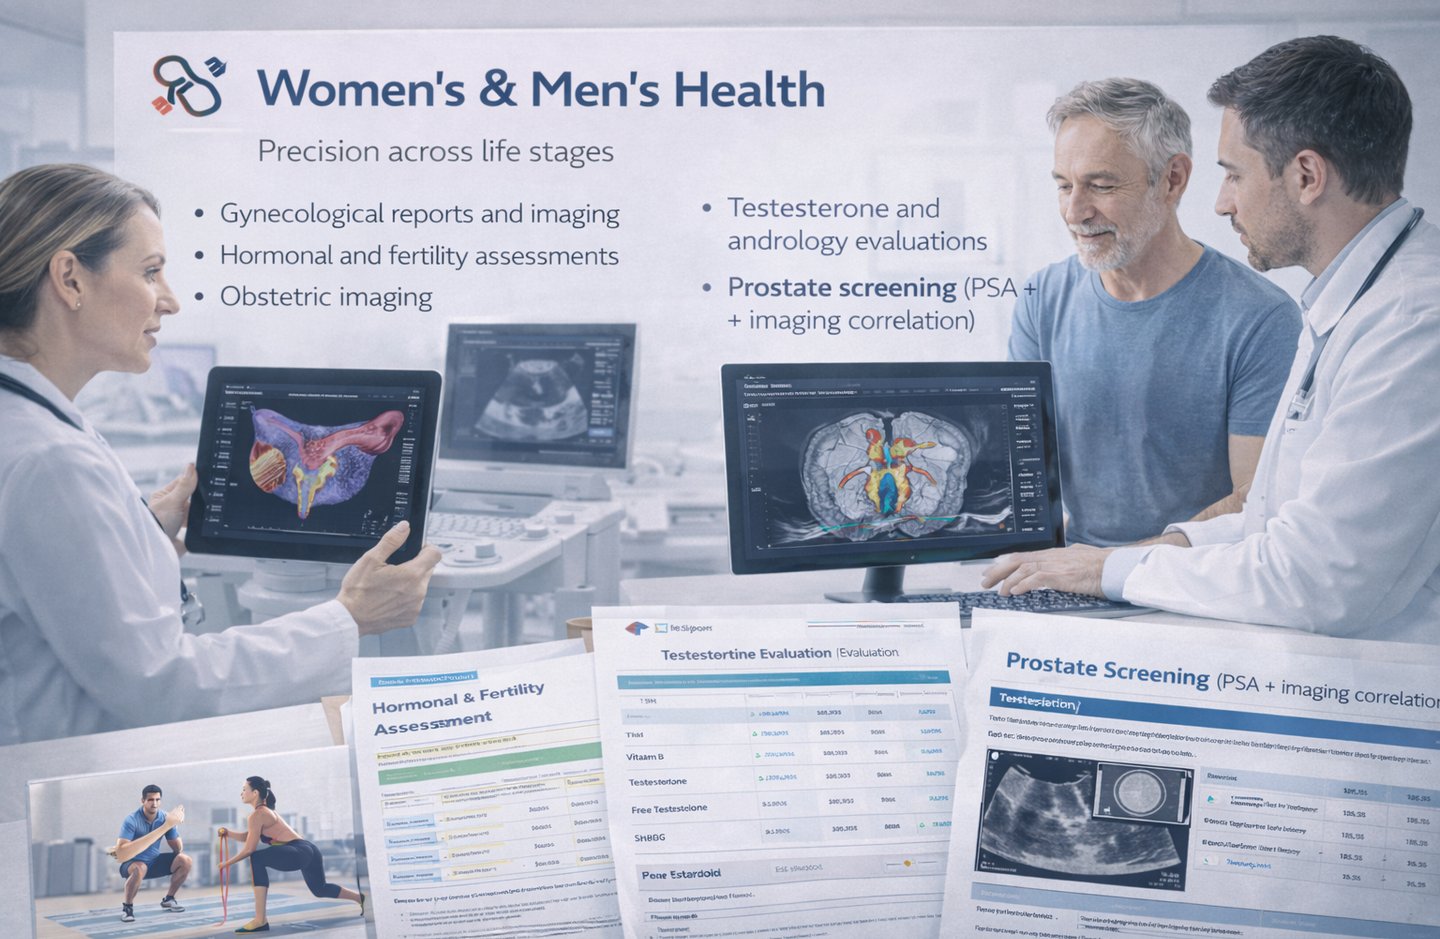

⚕️ Women’s & Men’s Health

Precision across life stages

Gynecological reports and imaging

Hormonal and fertility assessments

Obstetric imaging

Testosterone and andrology evaluations

Prostate screening (PSA + imaging correlation)